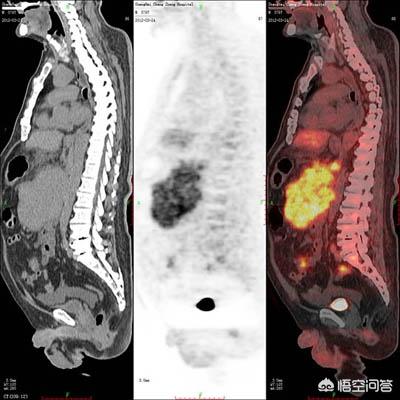

1.PET-CT(ポジトロンCT):

現在、PET-CTは約1万ドルで、より高価な検査とされ、払い戻しはできない。PET-CTは、陽電子放出核種を使ってグルコース、脂肪酸、アミノ酸、水などを標識し、陽電子スキャナーを使って体内の化学画像を得る原理に基づいており、主に早期の腫瘍の診断に用いられ、現在最も感度の高い検査方法である;

(1) PET/CT

PET/CTは非常に高価な検査で、全身PET/CT検査は8,000~10,000ドルかかり、健康保険で償還されません。PET/CTは、腫瘍の部位、浸潤の程度、遠隔転移の有無などを評価する非常に重要な検査です。PET/CT検査を健康診断に使用できるかという質問もあるが、それは不可能である。なぜなら、PET/CT検査は高価であり、偽陽性が出やすいからである。また、PET/CT検査は放射性であり、ルーチンの健康診断には推奨されないからである。

4.PET/CT検査

この検査は、より身近なものかもしれないが、非常に高価で、通常8,000ドル以上する。主に体内のがん病変の検出に使われ、患者のてんかん病変の判定にも使われる。

1.PET-CT

7,000~9,000ドルで、地域によって価格が変動する。日常的な健康診断には使われず、たとえ大金持ちであっても、この検診を利用することは勧められない。さらに言えば、初期がんのスクリーニングには使用できず、放射線量が増えるだけでなく、発見できない初期がんもある。この検査は主に腫瘍患者の良性・悪性判定、腫瘍の病期分類、転移、効果判定に使用されます。